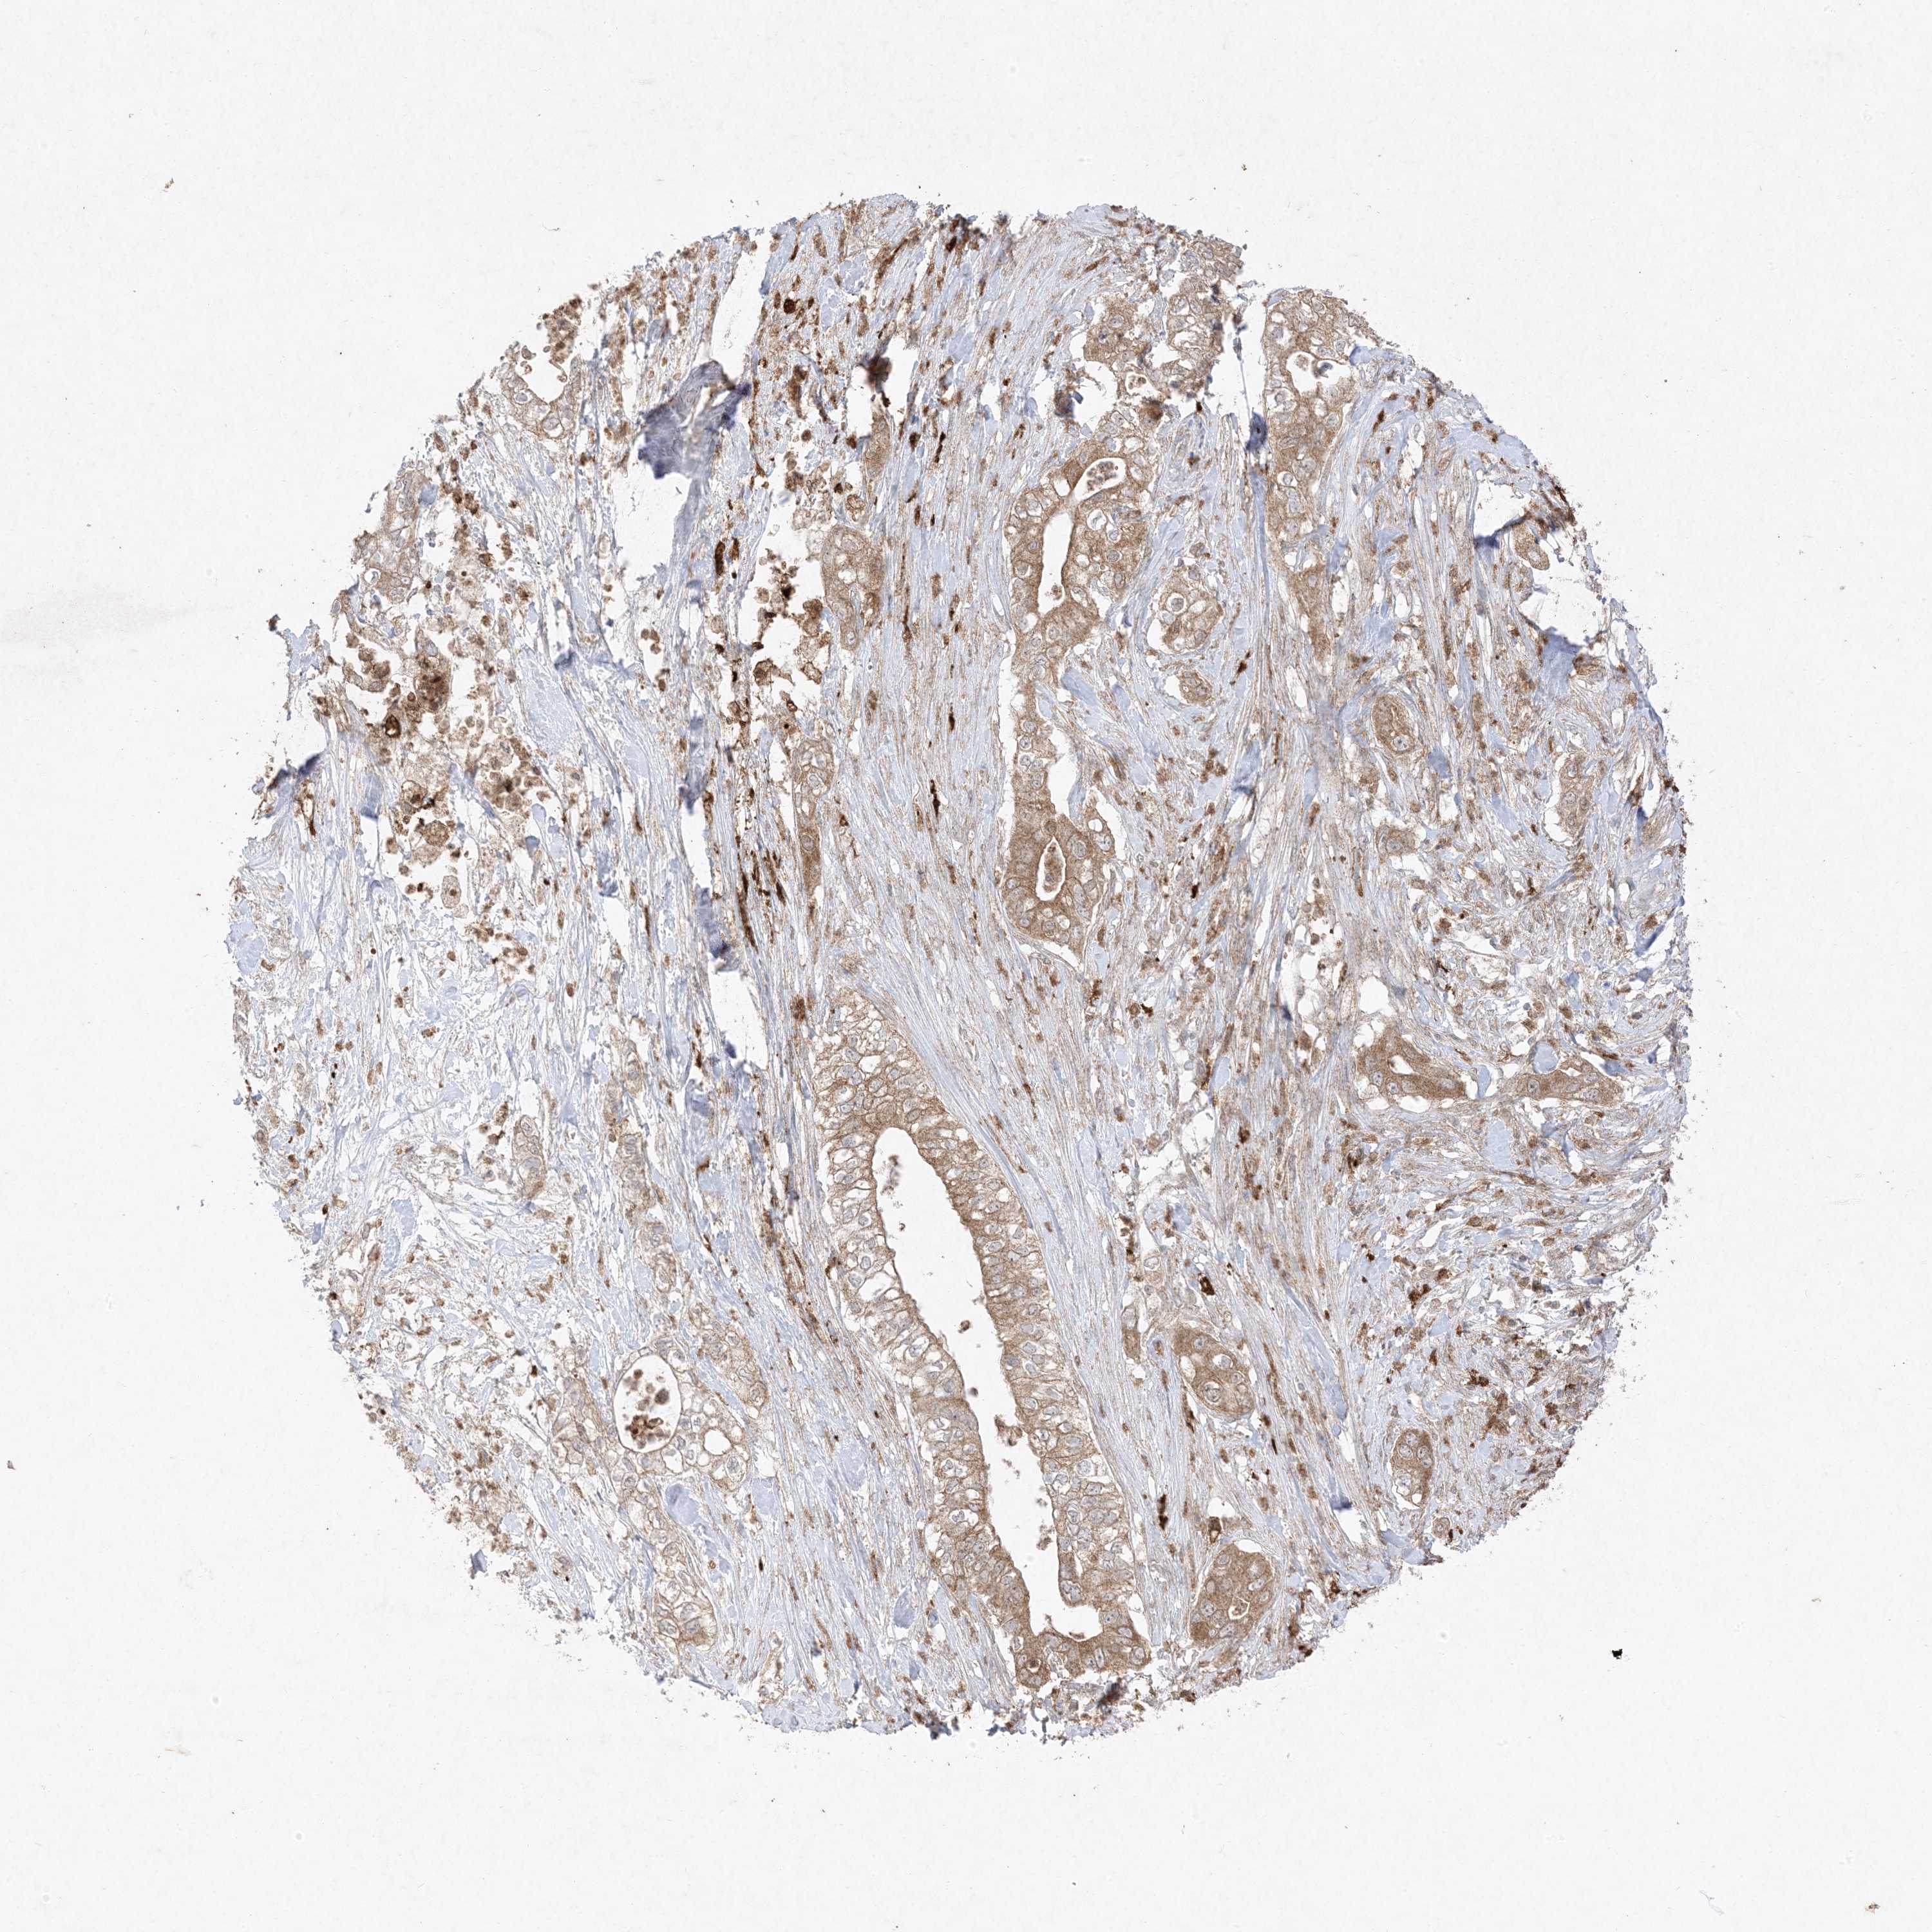

PANCREATIC CANCER - Protein expressioni

A mouse-over function shows sample information and annotation data. Click on an image to view it in a full screen mode. Samples can be filtered based on level of antibody staining by selecting one or several of the following categories: high, medium, low and not detected. The assay and annotation is described here.

Note that samples used for immunohistochemistry by the Human Protein Atlas do not correspond to samples in the TCGA dataset.

Antibody stainingi

Antibody staining in the annotated cell types in the current human tissue is reported as not detected, low, medium, or high, based on conventional immunohistochemistry profiling in selected tissues. This score is based on the combination of the staining intensity and fraction of stained cells.

Each image is clickable and will lead to virtual microscopy that enables deeper exploration of all samples and also displays staining intensity scores, fraction scores and subcellular localization as well as patient and tissue information for each sample.

Antibody HPA054975

Antibody CAB011464

Antibody CAB035990

Antibody CAB080407

Adenocarcinoma, NOS

Adenocarcinoma, metastatic, NOS